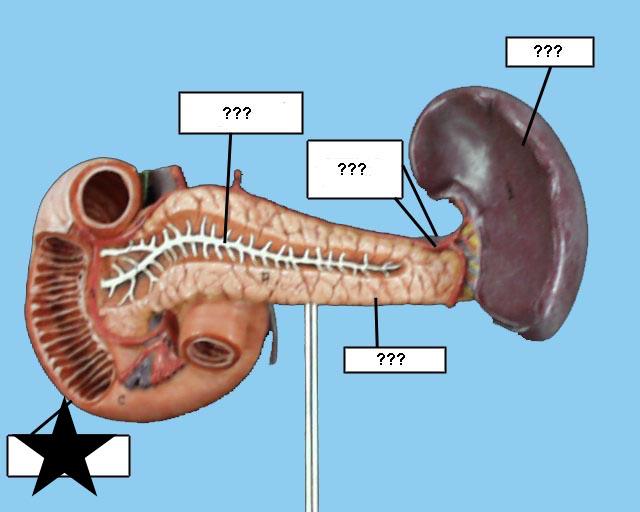

(Common) Hepatic Duct

Common bile duct

Common hepatic artery

Cystic duct

Duodenum

Gall bladder

Hepatic portal vein

Kidney

Liver

Pancreas

Pancreatic duct

Splenic artery/vein